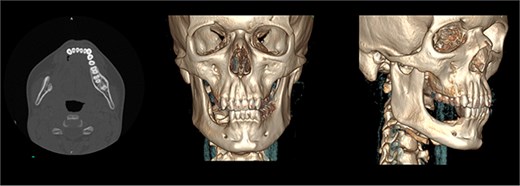

The patient was admitted from the clinic for urgent evaluation. Routine blood investigations were normal. An orthopantomogram revealed displacement of the second and third molars and a poorly defined superior margin of the alveolar process, suggesting osseous involvement (Fig. 2). Contrast-enhanced computed tomography (CT) of the facial bones and neck demonstrated a well-defined lucent lesion within the mandibular body with exophytic soft tissue extension into the oral cavity (Fig. 3). Magnetic resonance imaging (MRI) of the neck illustrated the hyperintense soft-tissue component with no rim enhancement or necrosis (Fig. 4). There was no lymphadenopathy noted clinically or radiograpgically.

CT showing well defined lucent lesion within the body of the right side of the mandible with exophytic soft tissue component extending into oral cavity.

The postoperative course was uneventful, and the patient was discharged on the first postoperative day. At 3 months postoperatively, follow-up CT imaging (Fig. 8) confirmed no evidence of recurrence. At 6 months, the patient remained symptom-free with normal oral intake and no clinical signs of recurrence.